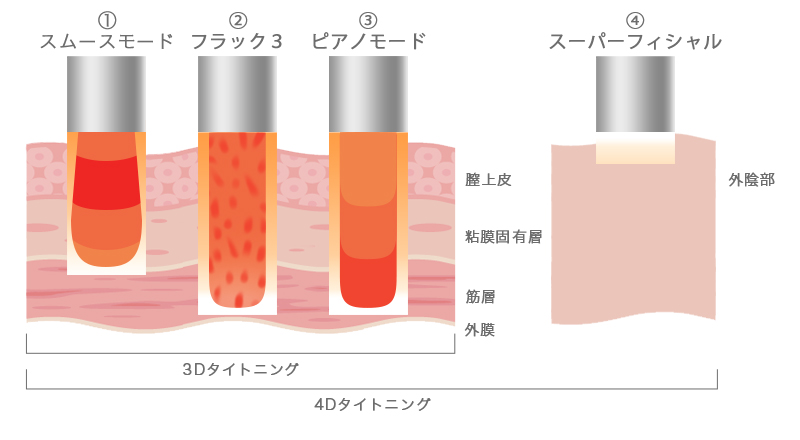

3Dタイトニング・4Dタイトニングとは

最上位機種で膣引き締め治療が可能

従来のレーザー治療や高周波治療は単一の種類、単一の波長による刺激で膣壁細胞を活性化させていました。

3Dタイトニング4Dタイトニングはエルビウムヤグレーザーとネオジウムヤグレーザーの2種類の組み合わせでさらにマルチプルモードによる複数の波長を出す世界最新の膣引き締め治療です。

膣壁の細胞に様々な角度から刺激を与え膣の奥深く、さらに広範囲にむらなく高いエネルギーを与え、さらなるコラーゲンの新生、引き締め効果アップが期待できます。

| 3Dタイトニング | 4Dタイトニング | ||

| Er:YAG | ①スムースモード(スーパーロングパルスエルビウム)

超ロングパルスのエルビウムヤグレーザーを照射し、粘膜下に熱溜まりを作ることで、膣粘膜最深部までコラーゲンの再構築を図ります。 フィラーを注入したように膣内粘膜がふっくらとします。 |

○ | ○ |

| Nd:YAG | ②フラック3(ショートパルスヤグ)パルス幅が短く、ピークパワーの高いネオジウムヤグレーザーを照射することで膣粘膜表面にほとんど傷つけることなく、3次元的に60℃以上の過熱を引き起こし、膣内部をしっかりと再構築するモードです。立体的に膣を引き締めることが可能です。 | ○ | ○ |

| Nd:YAG | ③ピアノモード(スーパーロングパルスヤグ)超ロングパルスのネオジウムヤグレーザーで組織の温度を42℃前後にあげていきます。レーザーの中でも最も深い所まで届くモードでその深さはcm単位となります。フラック3やスムースモードと併用することで更にコラーゲンが増生します。 | ○ | ○ |

| Er:YAG | ④スーパーフィシャル(ショートパルスエルビウム)短いパルス幅のエルビウムヤグレーザーを使用して、軽くピーリングをします。外陰部の黒ずみが気になる部分を明るくすることが可能です。 | – | ○ |